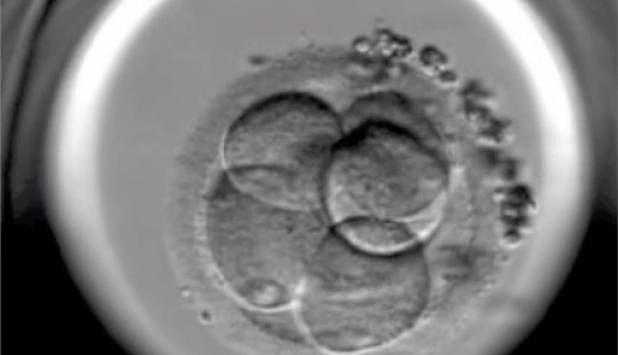

Los nacimientos in vitro

En 2000 nació el primer bebé "a la carta" libre de la Anemia de Fanconi que padecía su hermana y cuyas células de cordón sirvieron para curarla. La técnica de análisis embrionario (diagnóstico preimplantación tras fecundación in vitro) nos permite evitar el nacimiento de niños con determinadas enfermedades hereditarias.